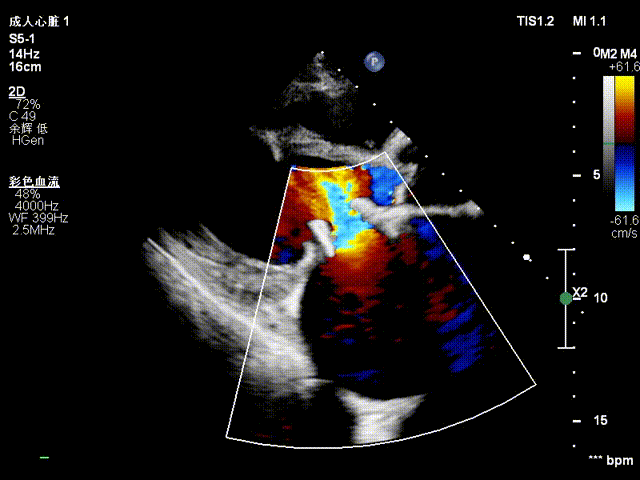

该患者为69岁老年男性,于2013年3月因风湿性心脏病二尖瓣重度狭窄合并冠心病进行冠状动脉搭桥手术联合二尖瓣生物瓣置换术,此次因反复胸腔积液至当地医院予以纠正心衰药物治疗,超声检查提示人工二尖瓣狭窄并重度关闭不全,人工二尖瓣返流,左心房显著增大。

瓣膜释放后显示人工瓣膜位置良好、微量瓣周漏,跨二尖瓣平均压差为5mmHg,顺利完成手术。